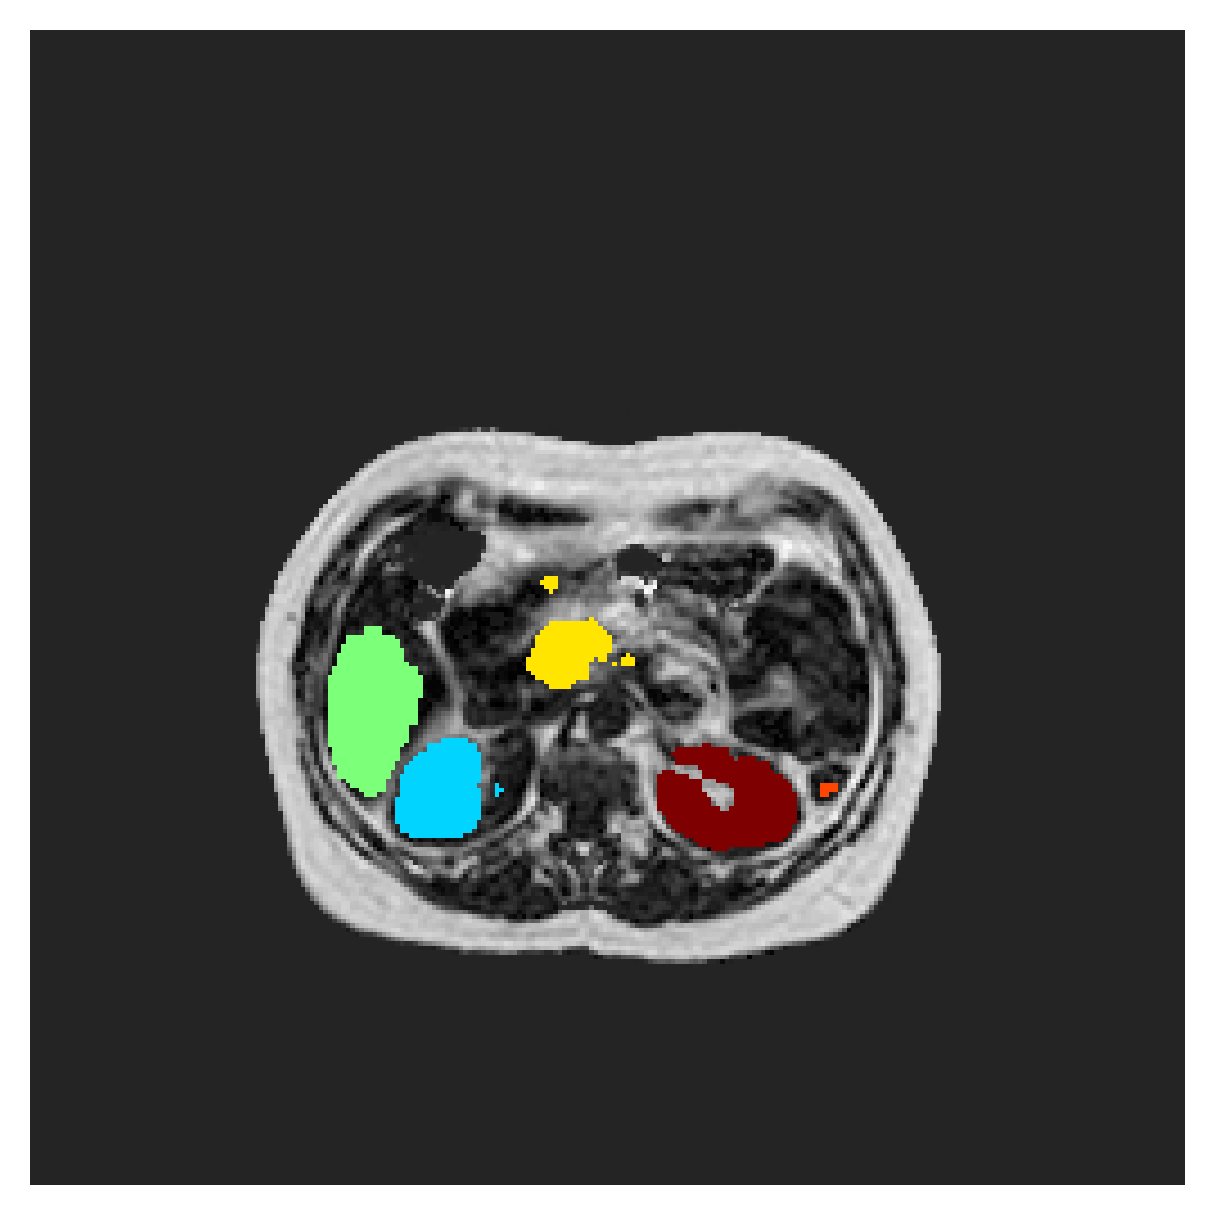

We normalize the volumes and resize the slices to pixels. As the official dataset comes with full annotations, we create a synthetic point ground truth. This is done by first randomly choosing the centers of the point annotations within the class masks, followed by filling an ellipse with axes lengths of and (in pixels) around each center. The intersections of these elliptic discs with the underlying full annotations are then used as our point ground truth. See Figure 2 for an example of the created weak annotation mask. The point annotations are created for every slice, one for each foreground object present in the slice.

The images contain two channels, one for water and one for fat content. For training, we normalize the volumes (per channel) and use 2D slices in the coronal plane, sized . The weak annotations are created synthetically, following the same procedure as described for the ACDC dataset.